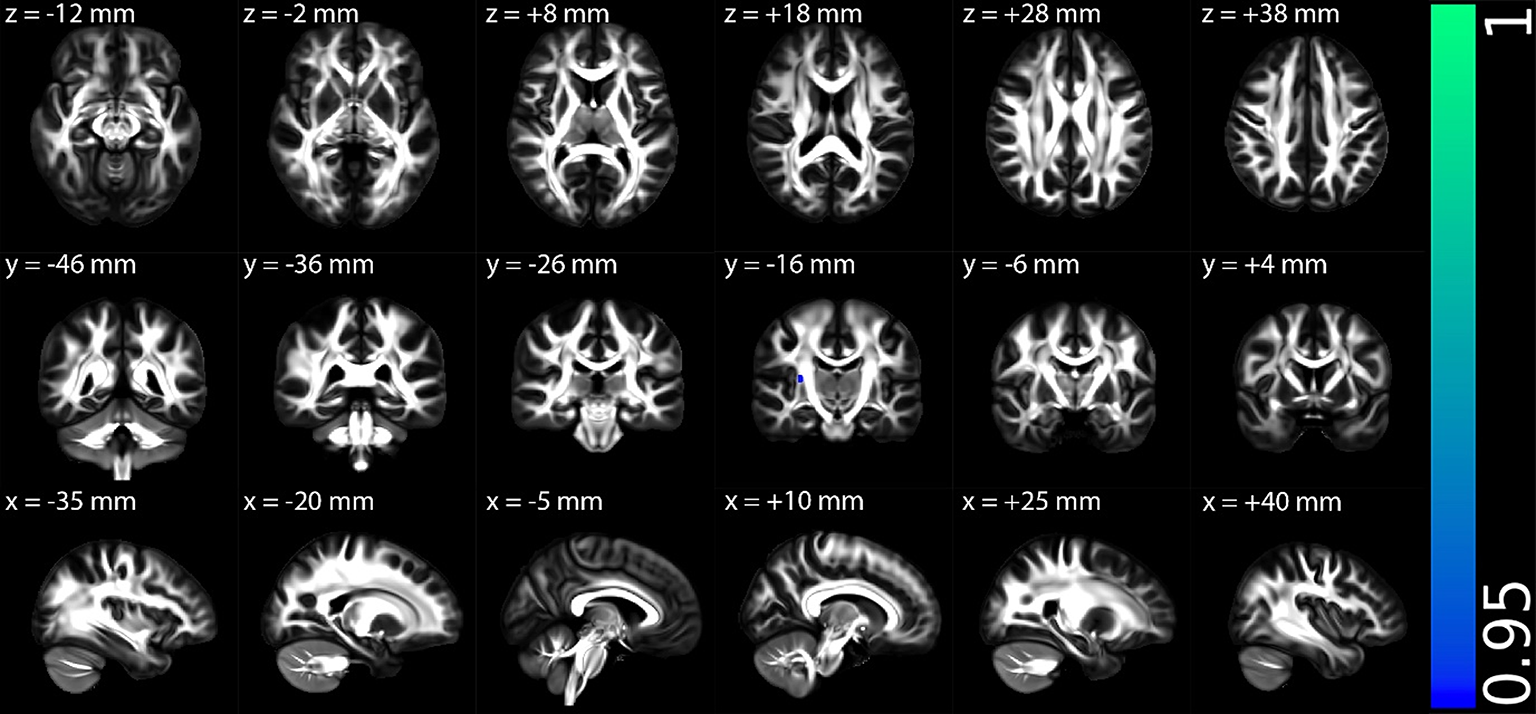

Fig. 4

The multiple regression results of axial diffusivity (AD) with disease duration for post-infectious ME/CFS (PI-ME/CFS) patient group. Results are displayed in Montreal Neurological Institute (MNI) 152 standard space based on the reference FSL_HCP1065 fractional anisotropy 1 × 1 × 1 mm standard-space image. The top row shows the results from six different axial slices, where the z-coordinates in MNI space from left to right are z = −12 mm, −2 mm, 8 mm, 18 mm, 28 mm, and 38 mm, respectively. The middle row shows the results from six different coronal slices, where the y-coordinates in MNI space from left to right are y = −46 mm, −36 mm, −26 mm, −16 mm, −6 mm, and 4 mm, respectively. The bottom row shows the results from six different sagittal slices, where the x-coordinates in MNI space from left to right are x = −35 mm, −20 mm, −5 mm, 10 mm, 25 mm, and 40 mm, respectively. Blue-green clusters show the significant negative correlation of AD with disease duration for PI-ME/CFS patient group. The colour bar represents 1-p values, with higher values indicating greater levels of statistical significance.